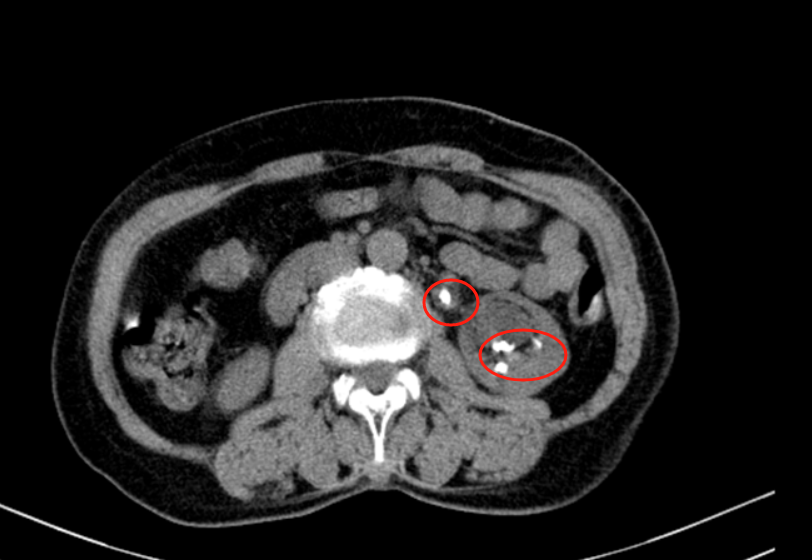

经过B超和CT检查,李主任发现王阿姨的左肾内布满结石,最大的结石直径超过1.5厘米,而且肾脏已经出现了重度积水。如果不及时治疗,肾功能可能会进一步受损,甚至危及生命。

面对王阿姨的病情,李主任建议进行经皮肾镜碎石取石术。这是一种微创手术,通过在腰部打一个“小孔”,用肾镜进入肾脏内部,将结石击碎并取出然而,王阿姨的手术并不简单:

左肾内结石数量多、分布广,手术需要尽可能清除所有结石,避免残留。但由于重度积水导致肾脏结构变形,手术视野受限,大大增加了操作难度!